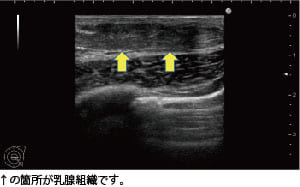

女性化乳房の治療前には、必ずエコー検査を実施

当院では女性化乳房の治療を行う際、必ず乳腺専用のエコーで検査を行って、原因を見極めたうえで治療を進めます。

このモニターゲストに関しては、皮下脂肪はそれほど多くなかったものの、乳腺の発達が認められましたので真性女性化乳房と診断しました。

当院では女性化乳房の治療を行う際、必ず乳腺専用のエコーで検査を行って、原因を見極めたうえで治療を進めます。

このモニターゲストに関しては、皮下脂肪はそれほど多くなかったものの、乳腺の発達が認められましたので真性女性化乳房と診断しました。